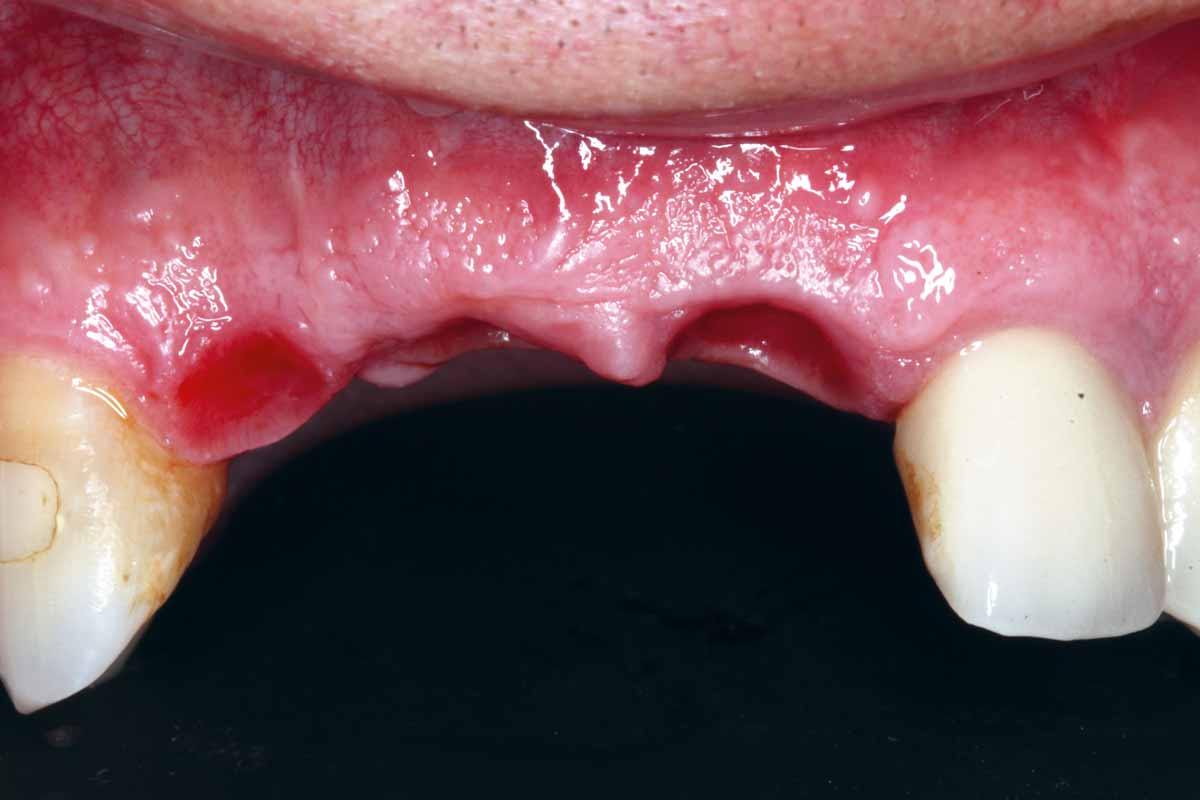

1/27 - Initial situation: missing teeth #11 & 12 and badly broken #21 root

GBR and soft tissue augmentation with cerabone® and mucoderm® - H. Maghaireh & V. Ivancheva